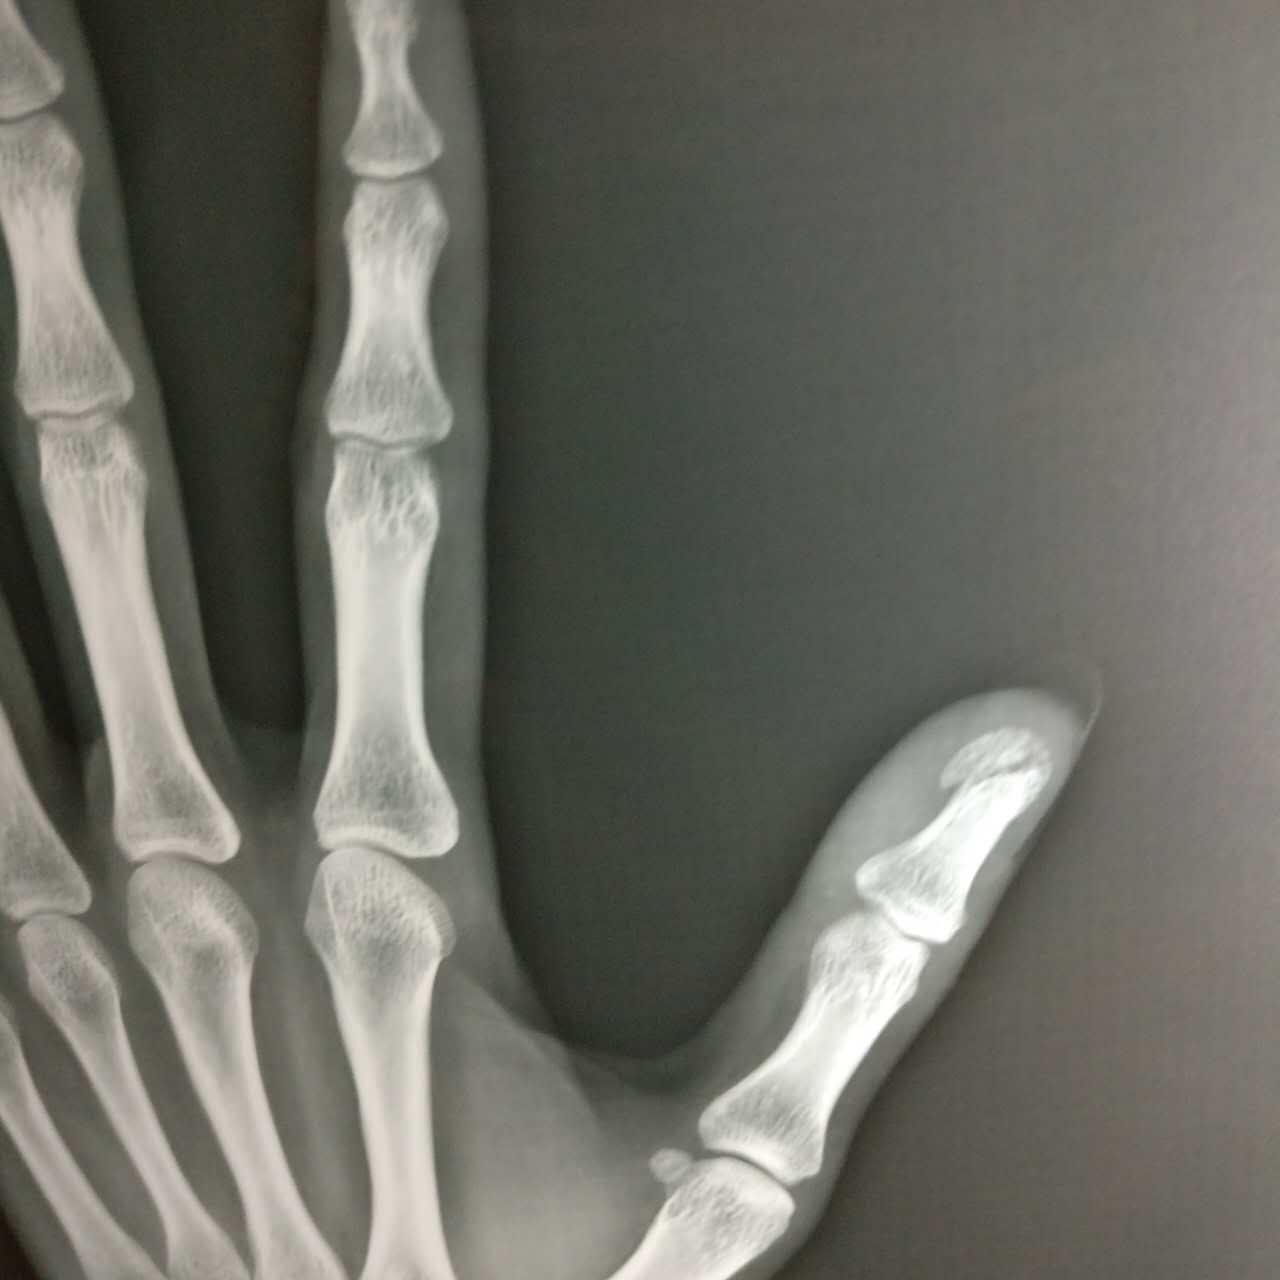

术前检查x拍片示,右食指末节指骨粉碎性骨折.

图片尺寸1080x1920